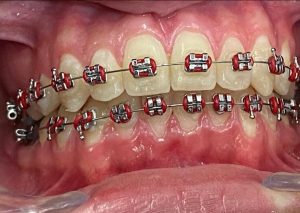

Tratamientos Ortodoncia Blanqueamiento dental Zoom Contacto 72 2795 9597 Marcar Ahora Envia whatsapp Visita nuestro facebook